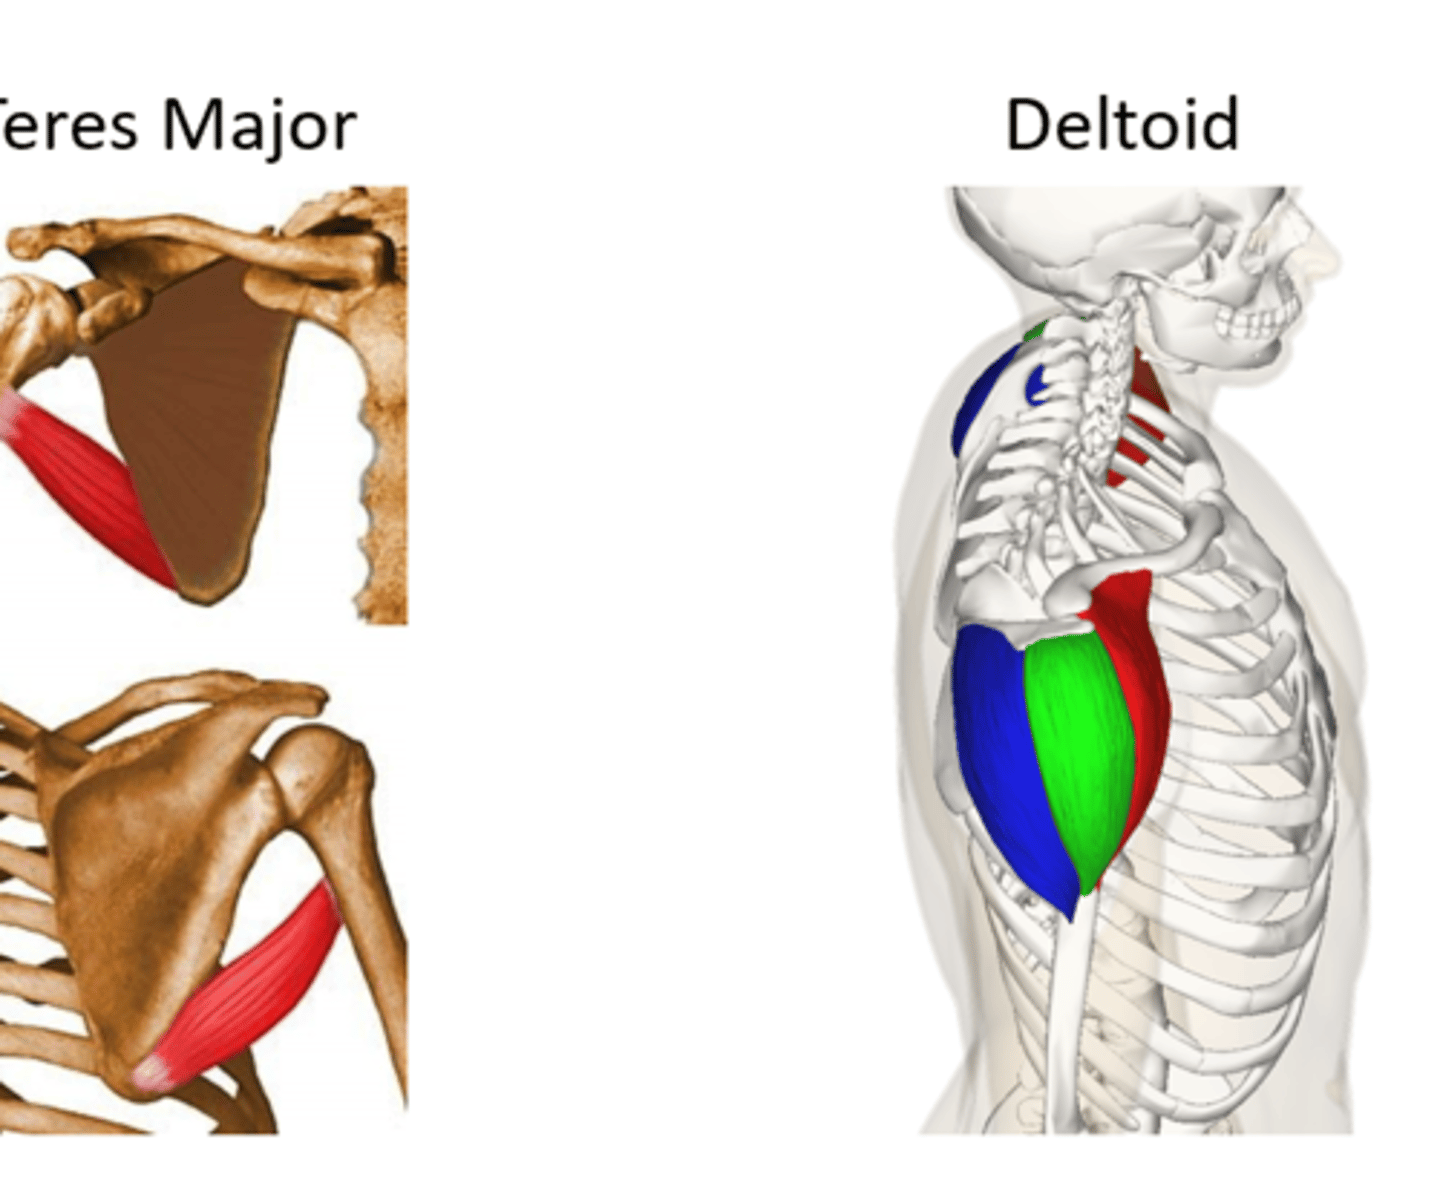

(Posterior axioappendicular and scapulohumeral muscles:)

Scapulohumeral muscles (intrinsic shoulder)

Deltoid and Teres Major

(Scapulohumeral muscles (intrinsic shoulder):) Deltoid

-Divided into anterior (clavicular), middle (acromial), and posterior (spinal) parts

-Flexes and medially rotates arm (anterior), abducts arm (middle), extends and laterally rotates arm (posterior)

-Axillary n. (C5 - C6)

-Abducts the arm after the initial 15˚. During the initial 15˚ is assisted by the supraspinatus muscle

(Scapulohumeral muscles (intrinsic shoulder):) Teres Major

-Adducts and medially rotates arm

-Lower subscapular n. (C5 - C6)

(Scapulohumeral muscles (intrinsic shoulder):) Rotator cuff muscles

Supraspinatus, Infraspinatus, Teres Major, Subscalpularis

(Rotator Cuff Muscles:) Teres Major

-Laterally rotates arm

-Axillary n. (C5 - C6)